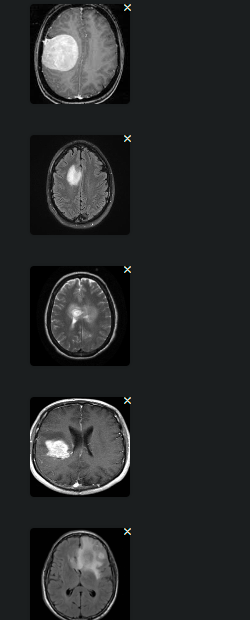

We have successfully integrated vision capabilities into our project, enabling the retrieval and analysis of medical images and videos. Key accomplishments include:

Image Retrieval: We implemented an endpoint (/record/image/search/{patientId}) that retrieves diagnostic images for a given patient, providing detailed insights such as lesion location, signal heterogeneity, and mass effects from MRI scans.

AI-Generated Observations: The system analyzes retrieved images and generates AI-powered observations and potential differential diagnoses (e.g., glioma, metastasis) based on the visual characteristics, while cautioning users to seek professional medical interpretation.

Comprehensive Imaging Feedback: For each patient, we deliver a comprehensive diagnostic result, including additional considerations like possible midline shifts, surrounding edema, and recommendations for further investigation, improving clinical decision-making.

This forms the foundation for leveraging advanced image recognition and diagnostic support in medical contexts.